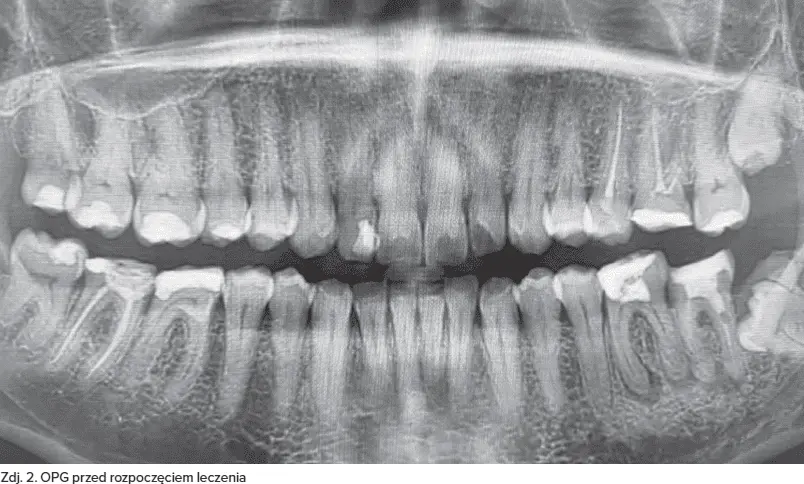

45-letni pacjent zgłosił się do poradni protetyki stomatologicznej w celu oceny oraz odbudowy zębów w żuchwie. Zlecono wykonanie badania TK żuchwy – badania OPG (zdj. 1A–J).

Na podstawie badania klinicznego oraz badań obrazowych stwierdzono znaczne zniszczenie twardych tkanek zębów oraz zmiany w okolicy okołowierzchołkowej zębów 36, 37, zajęcie furkacji zęba 37 oraz obecność zatrzymanego zęba 38.

Po konsultacji z chirurgiem stomatologicznym stwierdzono, że zęby 36, 37 nie nadają się do odbudowy protetycznej. Zęby 36, 37 zakwalifikowano do ekstrakcji z natychmiastową reg...